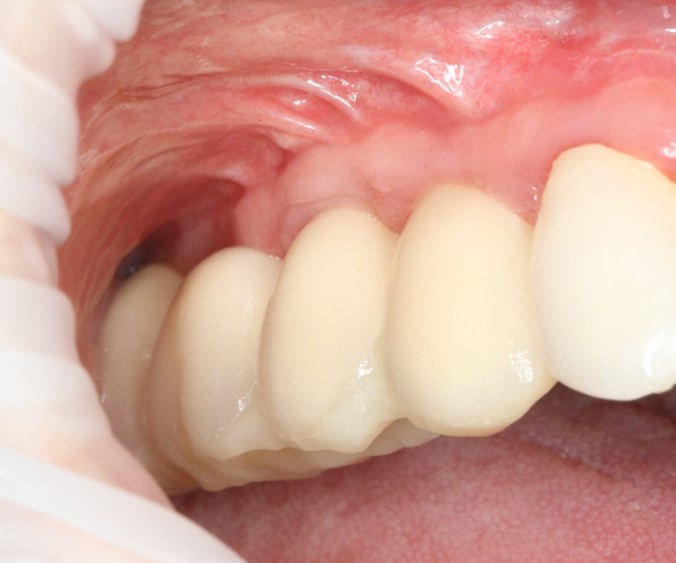

Поэтому после удаления зуба мы ждём, в общей сложности, около 4-8 недель, затем приступаем к имплантологическому лечению. Хотя, иногда бывают ситуации, когда мы делаем синуслифтинг одномоментно с удалением зуба, а сам имплантат ставим попозже:

через 4 месяца: